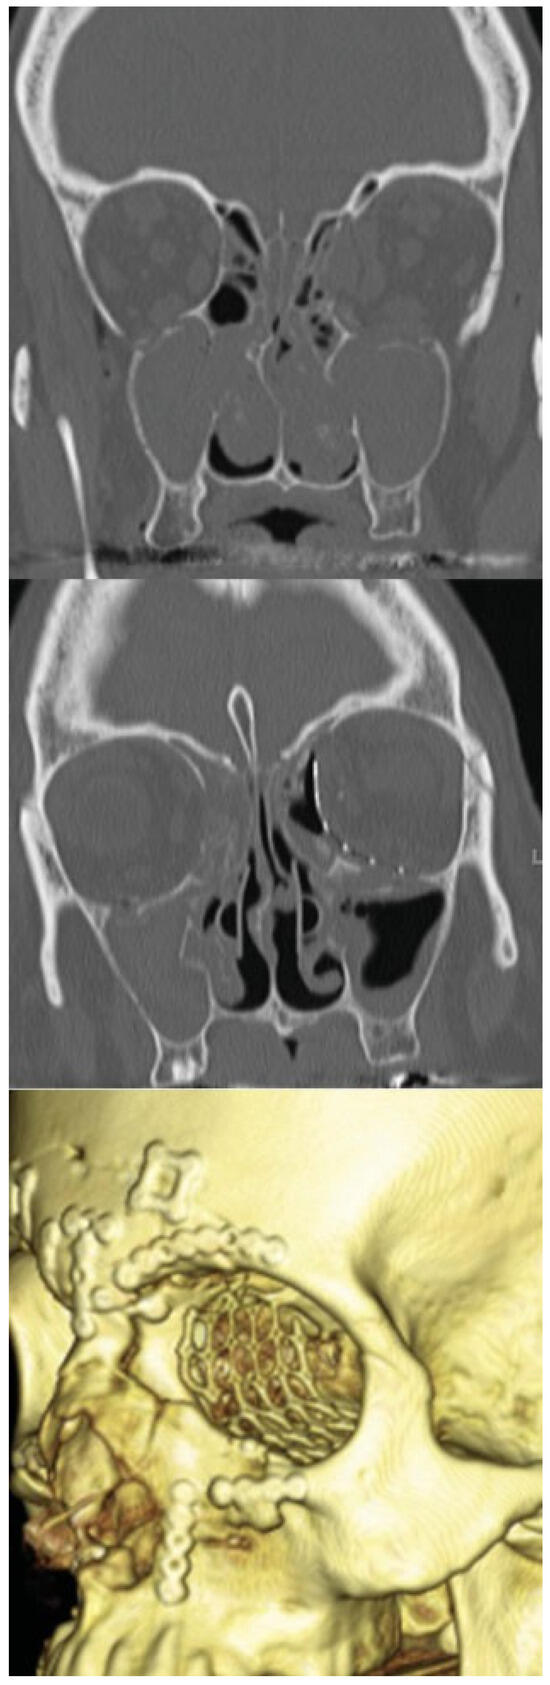

Isolated medial orbital wall fractures were reconstructed with single MEDPOR (Stryker) implants. Combined medial wall and floor fractures were reconstructed with MEDPOR TITAN implants; a single implant was used in seven patients, and two implants were used in one patient (to avoid the need to divide the inferior oblique muscle) (see ►Figure 5). Excellent exposure was achieved in all cases. No intraoperative complications were encountered.

Figure 5. A 48-year-old man with a large left-side combined orbital floor and medial orbital wall blowout fracture from an assault. Fracture area was 7.8 cm2 and was covered with two separate pieces of MEDPOR TITAN implant, divided to avoid transection of the inferior oblique muscle. Preoperative scan (top), postoperative scan (middle), and postoperative 3D rendering (bottom).